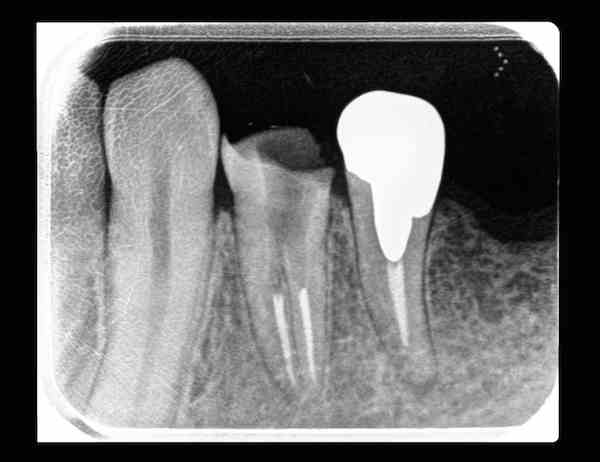

標準根管数と異なる場合2015年10月29日ydo約2分診療室 TweetShare on Tumblr【 標準根管数と異なる場合は、実際の根管数での請求をしてくださって構いませんが、その旨を適用記載して下さい 】 歯科関係者以外の方にはチンプンカンプンでしょうが、上記のようにお願い致します。なお、大臼歯4根管でEMRを4根管として請求なさる場合は適用記載は必要ありません。 ↓なんかが典型的なのですが、これは『介』の字のような根管形態なので楽勝だったのですが、根の途中から『万』の字のようだったりすることも多く、『尢』の字のようだったら絶対に心とリーマーが折れそうです。 横向きに見えることも珍しいかな? 割りとストレートでした